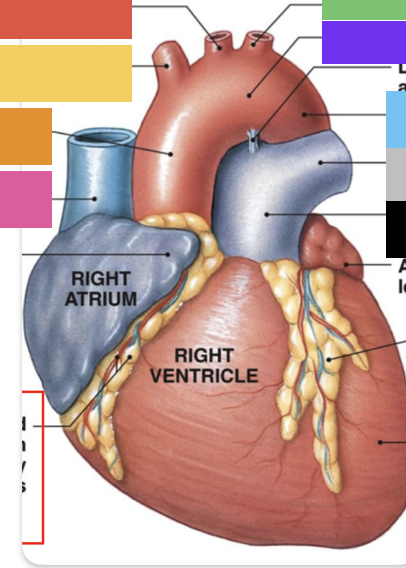

light purple

base

purple

apex

grey

right atrium

pink

right auricle

green

left atrium

green

left auricle

blue

right ventricle

orange

left ventricle